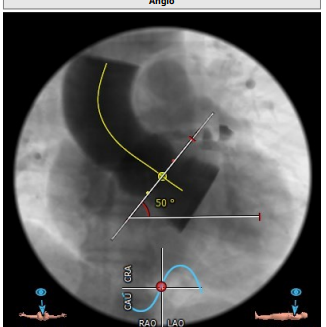

瓣环平均直径:21.1 mm,左室流出道平均直径:22.4mm。

升主动脉(未见)明显扩张,心脏角度:50°。

左冠高度:10.6mm,右冠高度:14.5mm。

钙化积分:61.2mm³,轻度钙化。